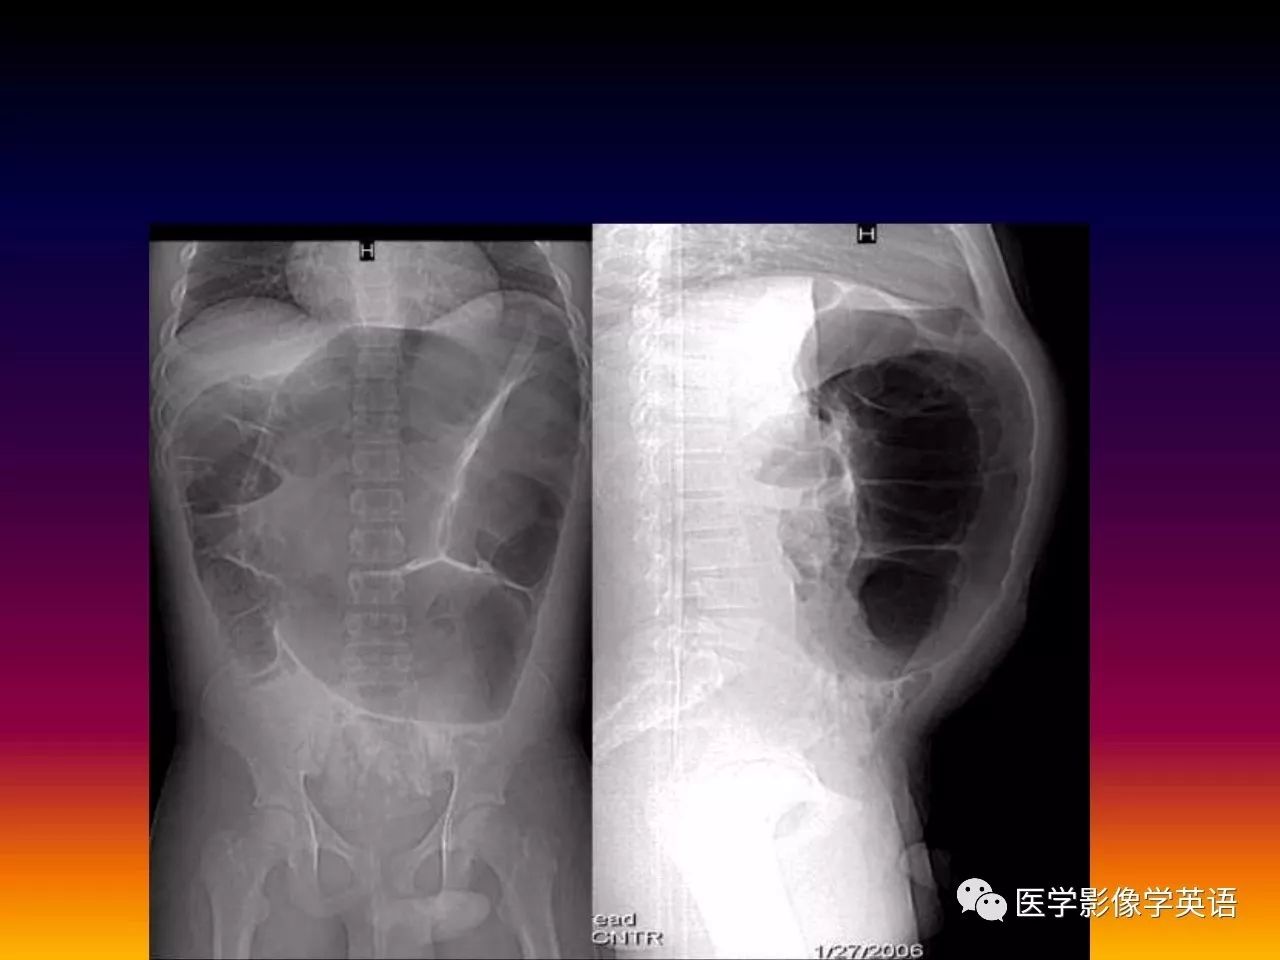

20. Plain radiography

21. Volvulus Gastric volvulus Intrathoracic stomach with air fluid level Midgut volvulus Double bubble sign Colonic volvulus Sigmoid Coffe bean sign Cecal Marked cecal distension

22. Gastric volvulus ? Intra-thoracic stomach with double air fluid level.

23. Gastric volvulus ? Intrathoracic stomach with double air fluid level.

24. Midgut volvulus ? Double bubble sign.